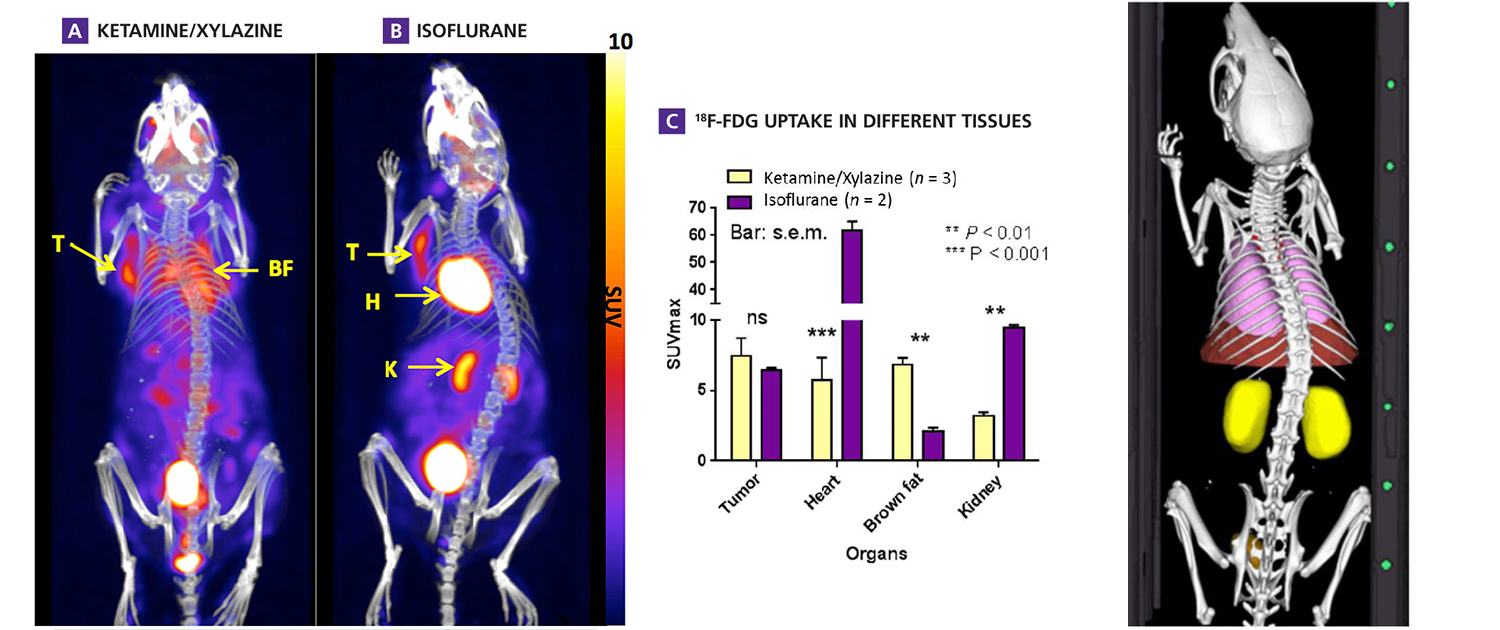

Image analysis is a critical component of clinical and preclinical imaging research, providing a means of quantifying and interpreting the data generated by imaging modalities such as PET, SPECT, and CT. In clinical imaging, image analysis is used to aid in diagnosis and treatment planning. For example, in oncology, image analysis can be used to assess the response to chemotherapy and radiation therapy, providing a means of monitoring the effectiveness of treatment and making adjustments as necessary.

In cardiology, image analysis can be used to evaluate blood flow and cardiac function, enabling the diagnosis and treatment of heart disease. In preclinical imaging research, image analysis plays a crucial role in the development of new treatments and therapies. Image analysis algorithms can be used to quantify the effects of drug treatments or surgical procedures on biological processes such as blood flow and metabolic activity. By providing a means of objectively assessing treatment efficacy, image analysis helps to optimize treatment protocols and improve patient outcomes.

The same image analysis techniques can be applied to both clinical and preclinical images, allowing for a seamless transition between research modalities. Moreover, image analysis has additional applications in clinical research, beyond the evaluation of disease progression or response to therapy. For example, image analysis can be used for radiation treatment planning to optimize the radiation dose and minimize side effects.

Image analysis can also be used to evaluate the efficacy of medical devices or surgical procedures. Additionally, image analysis can be used in radiomics, which involves the high-throughput extraction of large amounts of data from medical images, allowing for the identification of imaging biomarkers that can help in patient diagnosis and prognosis. Overall, image analysis is a powerful tool in both preclinical and clinical research, with a wide range of applications beyond disease evaluation.

At our company, we provide a wide range of image analysis services for both preclinical and clinical imaging research. Our team of experts has extensive experience in conducting image analysis for various modalities, including PET, SPECT, CT, and optical imaging. We offer a comprehensive set of services, such as image registration, segmentation, quantification, and statistical analysis. We understand the importance of accurate and precise image analysis in the success of research projects, and we use state-of-the-art software and techniques to deliver reliable and reproducible results.